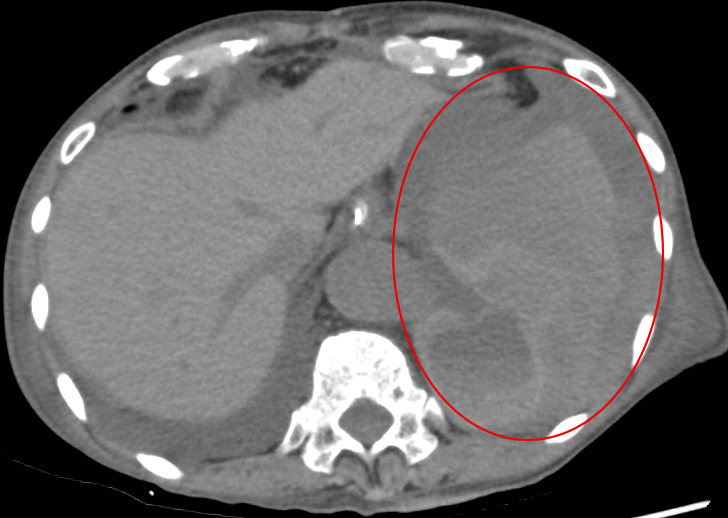

腎血管筋脂肪腫のIVR術前CT 腎血管筋脂肪腫のIVR術前CT 腎血管筋脂肪腫のIVR術前CT 2025-12-23 東京医科大学病院Revolution FrontierGE Healthcare2025 詳細はこちら